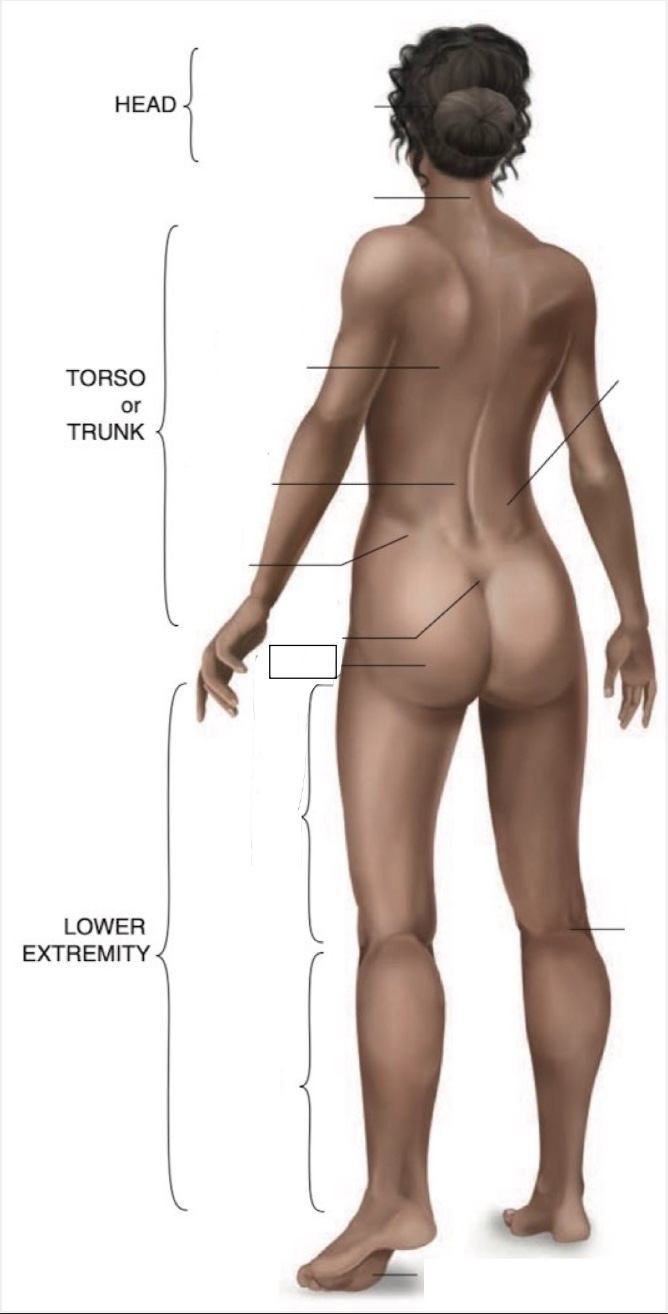

Occipital region

Cervical region

Inferior angle of scapula

Lumbar region

Iliac crest

Sacral region

Buttock

Flank